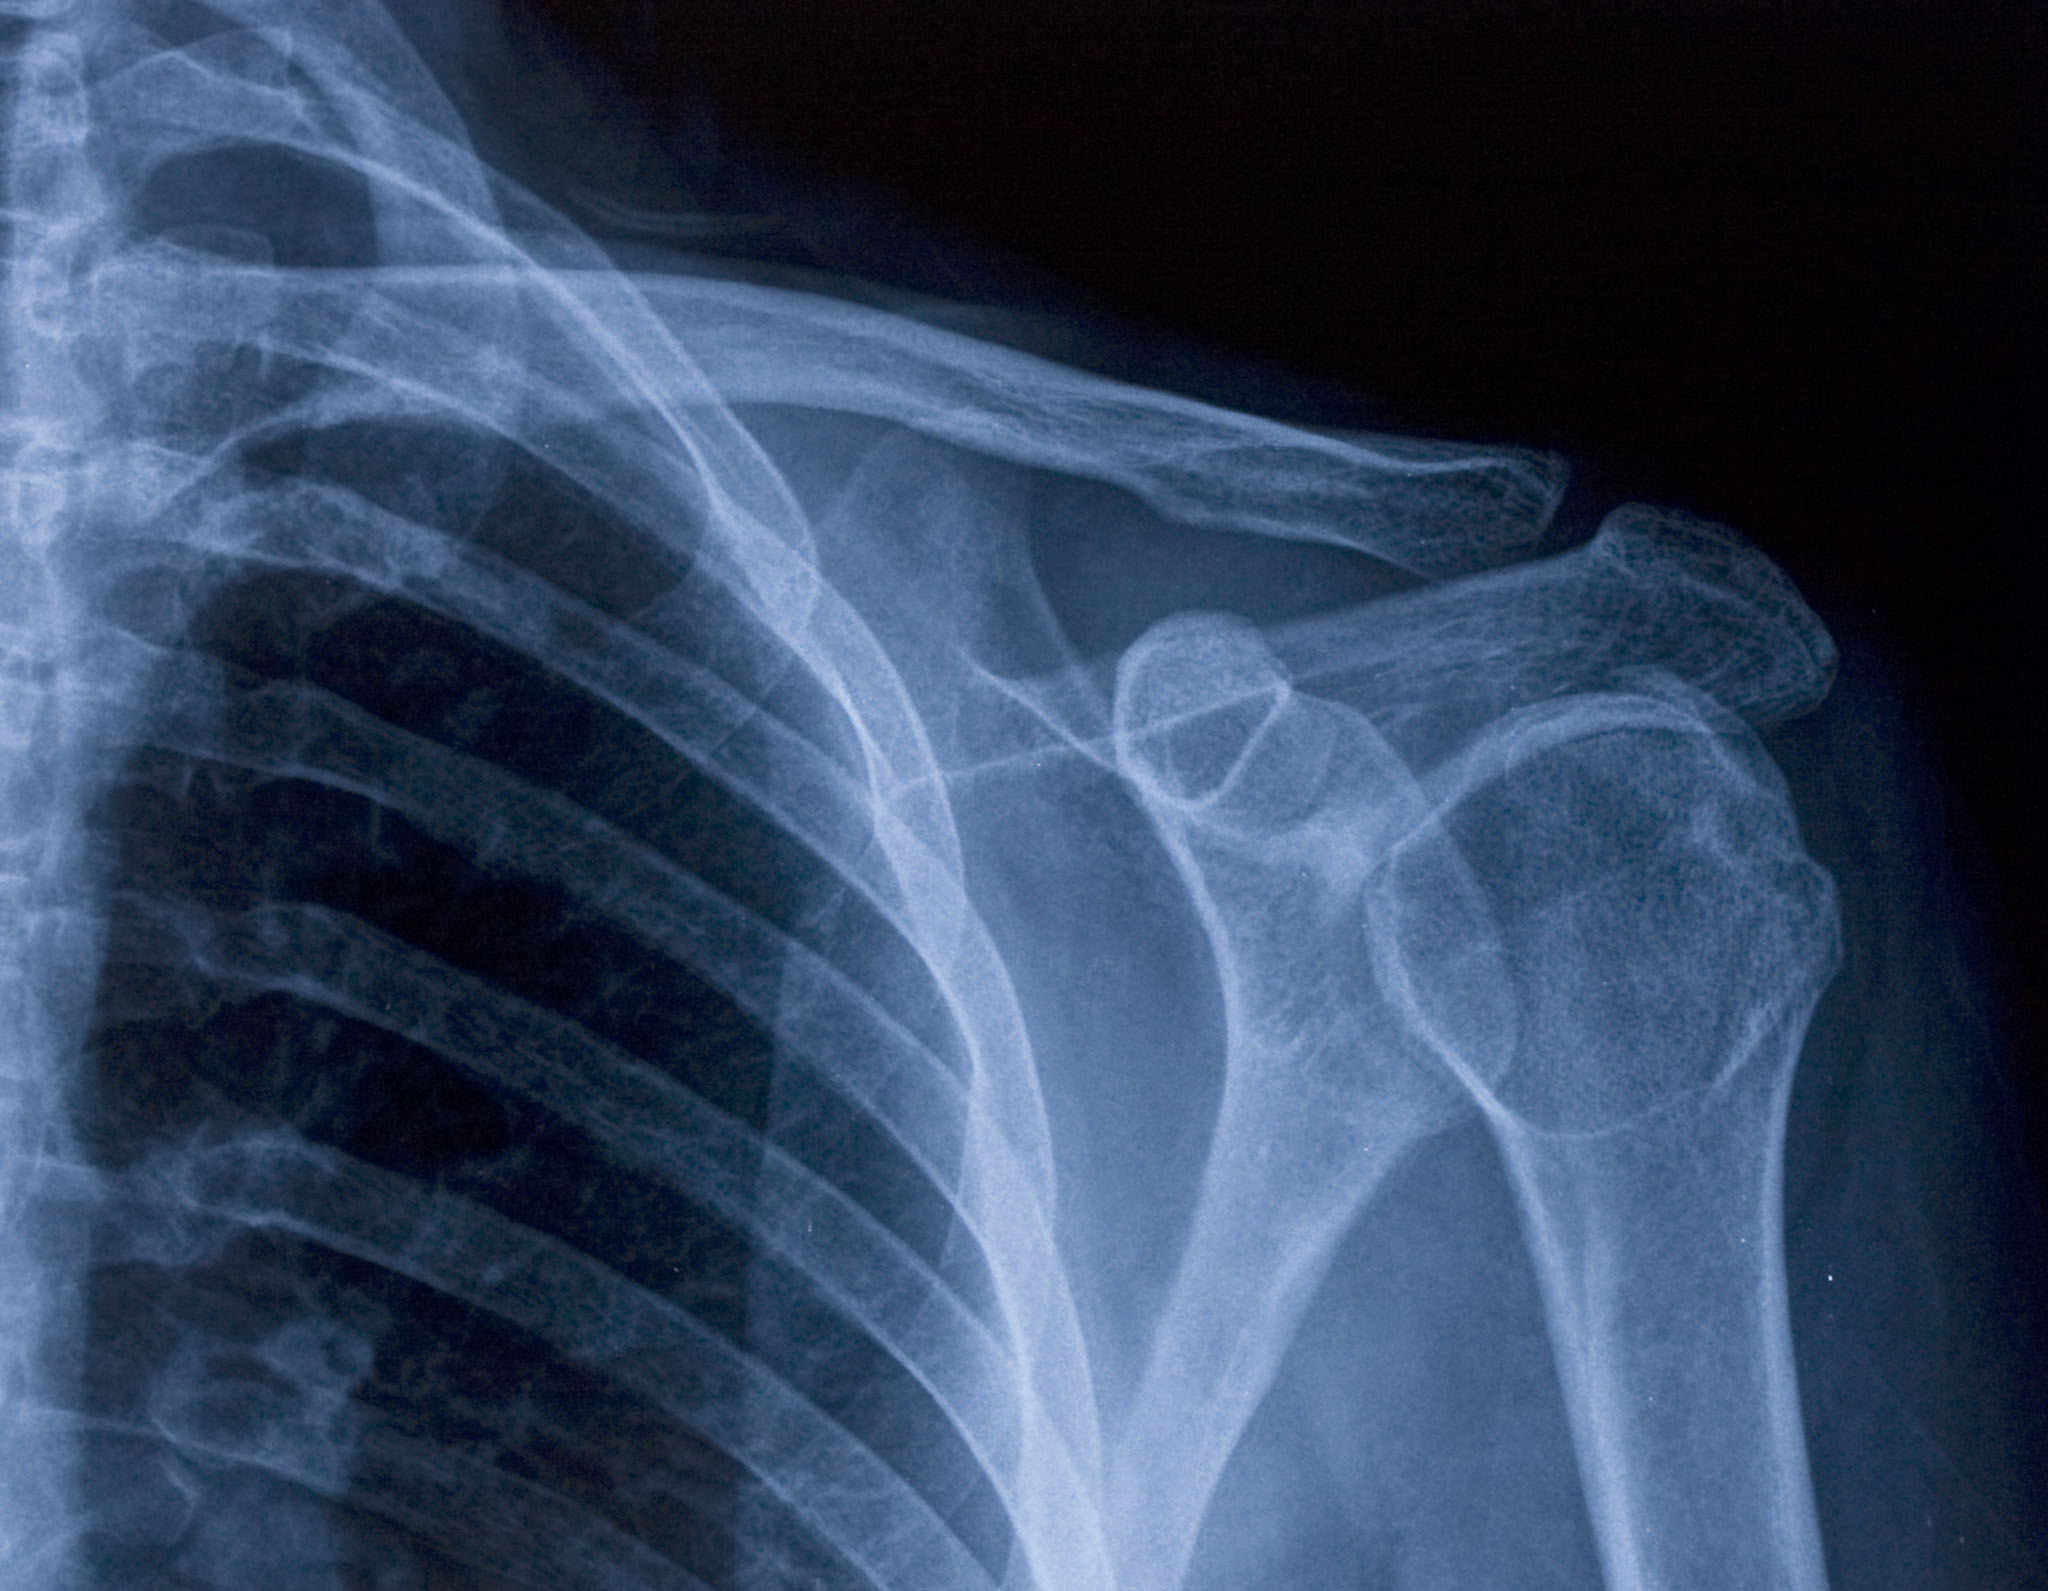

Diagnostic Imaging

Accurate diagnosis is the foundation of effective treatment. Our imaging services help identify injuries, confirm conditions, and assess the severity of issues affecting bones, joints, and soft tissue.

Shoulder to fingertip

The hands, wrist, forearm, elbow, and shoulder are critical to your daily function. Faced with even a slight injury or a disease of the bones, nerves, joints, and muscles can cause ongoing pain and be severely debilitating. At Phoebe, our experienced team of dedicated orthopaedic specialists provide comprehensive surgical and non-surgical medical care for a wide spectrum of bone and soft-tissue conditions of the hand and upper extremity. Our treatment options for fractures, arthritis, and mobility issues give you more functionality and less pain. With the largest orthopaedic team in Southwest Georgia, Phoebe provides the experience, technology, and personalized care needed to help you get back to daily life.